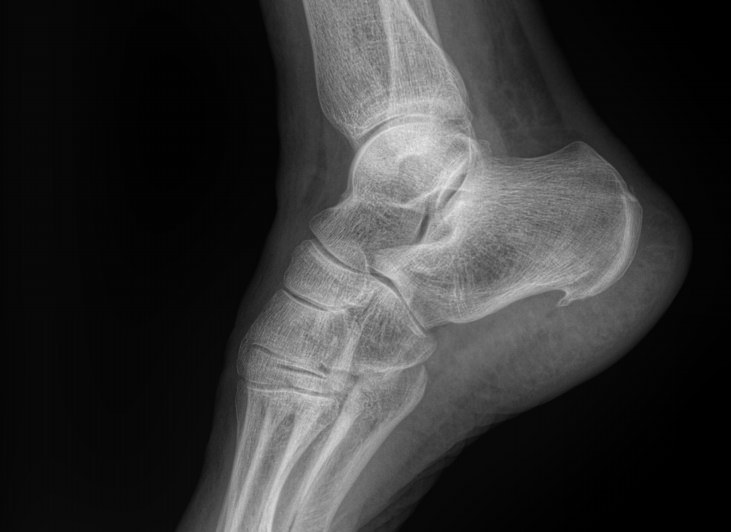

Назад Рентген пяточных костей в боковой проекции

Пяточная кость ― самая крупная среди костей стопы. Нагрузка, приходящаяся на нее, колоссальна. Отсюда и частая травматизация, связанная как со спортом, так и с бытовой и профессиональной деятельностью. Также все патологии, которые развиваются в костной ткани, могут появиться и в пяточной кости. Рентген ― наиболее часто назначаемый вид диагностики при поражении пятки.

На рентгенограмме будут отчетливо видны все структурные изменения, произошедшие с самой пяточной костью и тканями вокруг нее.

Что покажет рентген пяточных костей в боковой проекции

• Целостность кости: переломы, отломки, смещение;

• Состояние костной ткани: разрежение, склерозирование, некроз и другие изменения;

• Конгруэнтность суставных поверхностей и состояние щелей, попавших в область снимка: нормальные, измененные;

• Отечность и инородные тела в мягких тканях пятки;

• Новообразования: опухоли, остеофиты.

Стоит отметить, что остеофиты не являются причиной плантарного фасциита, а вырастают в ответ на хроническое раздражение мягких тканей и свидетельствуют о глубокой стадии заболевания.